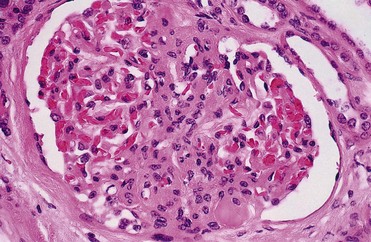

Renal obstruction produces tubular atrophy and cell death. The major mechanism by which tubular cells die is apoptosis, a process that is normally involved in postnatal development and tissue renewal in adults. The process can be triggered by both intrinsic and extrinsic factors and results in degradation and condensation of the nucleus. The cells are further degraded into apoptotic bodies, which are eventually phagocytized by healthy cells, usually without inducing inflammation. When rat kidneys are obstructed, renal tubular cell apoptosis begins in about 4 days and peaks after 15 days, with interstitial cell apoptosis continuing for the duration of obstruction (Choi et al, 2000). Glomerular cells appear to be resistant to obstruction-induced apoptosis. Pathological apoptosis of tubule cells from obstruction may secondarily trigger inflammatory responses from the release of cytokines and recruitment of leukocytes (Canbay et al, 2004).

Urinary tract obstruction leads to progressive and, eventually, permanent changes in the structure of the kidney, including the development of tubulointerstitial fibrosis, tubular atrophy and apoptosis, and interstitial inflammation. A number of cytokines and growth factors have been shown to play roles in these events, among which the most prominent include transforming growth factor beta TGF-β, angiotensin II, NFκB, and TNF-α. Some are produced directly from the renal tubular and interstitial cells; others are generated from infiltrating macrophages.

Tubulointerstitial fibrosis develops as a consequence of extracellular matrix being synthesized and deposited at a greater rate than it is degraded, as well as to a relative increase in matrix due to collapse of parenchymal volume as nephrons are destroyed (Hewitson, 2009). A family of enzymes known as matrix metalloproteinases (MMPs), which includes collagenase, normally cleaves and degrades the collagenous and noncollagenous components of the extracellular matrix. Obstruction increases the synthesis of tissue inhibitors of metalloproteinases (TIMPs) that reduce MMP activity, resulting in the accumulation of extracellular matrix. Infiltrating macrophages stimulate TGF-β synthesis, and this growth factor increases TIMP production, thus reducing collagen turnover. Macrophages also produce other cytokines and growth factors, such as interleukin 2, interleukin 6, fibroblast growth factor, and platelet-derived growth factor (PDGF), that appear to contribute to this inflammatory and fibrotic process. Active TGF-β binds directly to its type 2 receptor, which subsequently activates and phosphorylates the type 1 TGF-β receptor. Both of these receptors have been shown to be upregulated in rats with UUO, in both the obstructed and contralateral renal units. This may be a factor in the hypertrophic response sometimes seen in the nonobstructed kidney (Sutaria et al, 1998). The activated type 1 TGF-β receptor subsequently phosphorylates SMAD (mobile transcription factors with a name derived from related genes in Caenorhabditis elegans [Sma] and Drosophila [Mad]) proteins. A heteromeric complex of SMAD proteins translocates to the nucleus, where it interacts with transcription factors to regulate gene transcription (Wamsley-Davis et al, 2004) and stimulates tubulointerstitial fibrosis (Fukasawa et al, 2004). Stimulation of TGF-β furthermore stimulates the JNK1 (c-JUN N-terminal protein kinase 1) pathway, which targets the activation of c-Jun and activates transcription factor 2, which are critical components in activating fibronectin production. Increased mRNA expression of TGF-β is seen as early as 10 hours after obstruction and increases for 4 days (Walton et al, 1992; Diamond et al, 1994). The increase occurs primarily in medullary tubules and the interstitium and is less prominent in cortical tubules or glomeruli. Furthermore, TGF-β interacts with other profibrotic growth factors such as EGF and angiotensin II (Kaneto et al, 1993; Ishidoya et al, 1995; Chevalier et al, 1998).